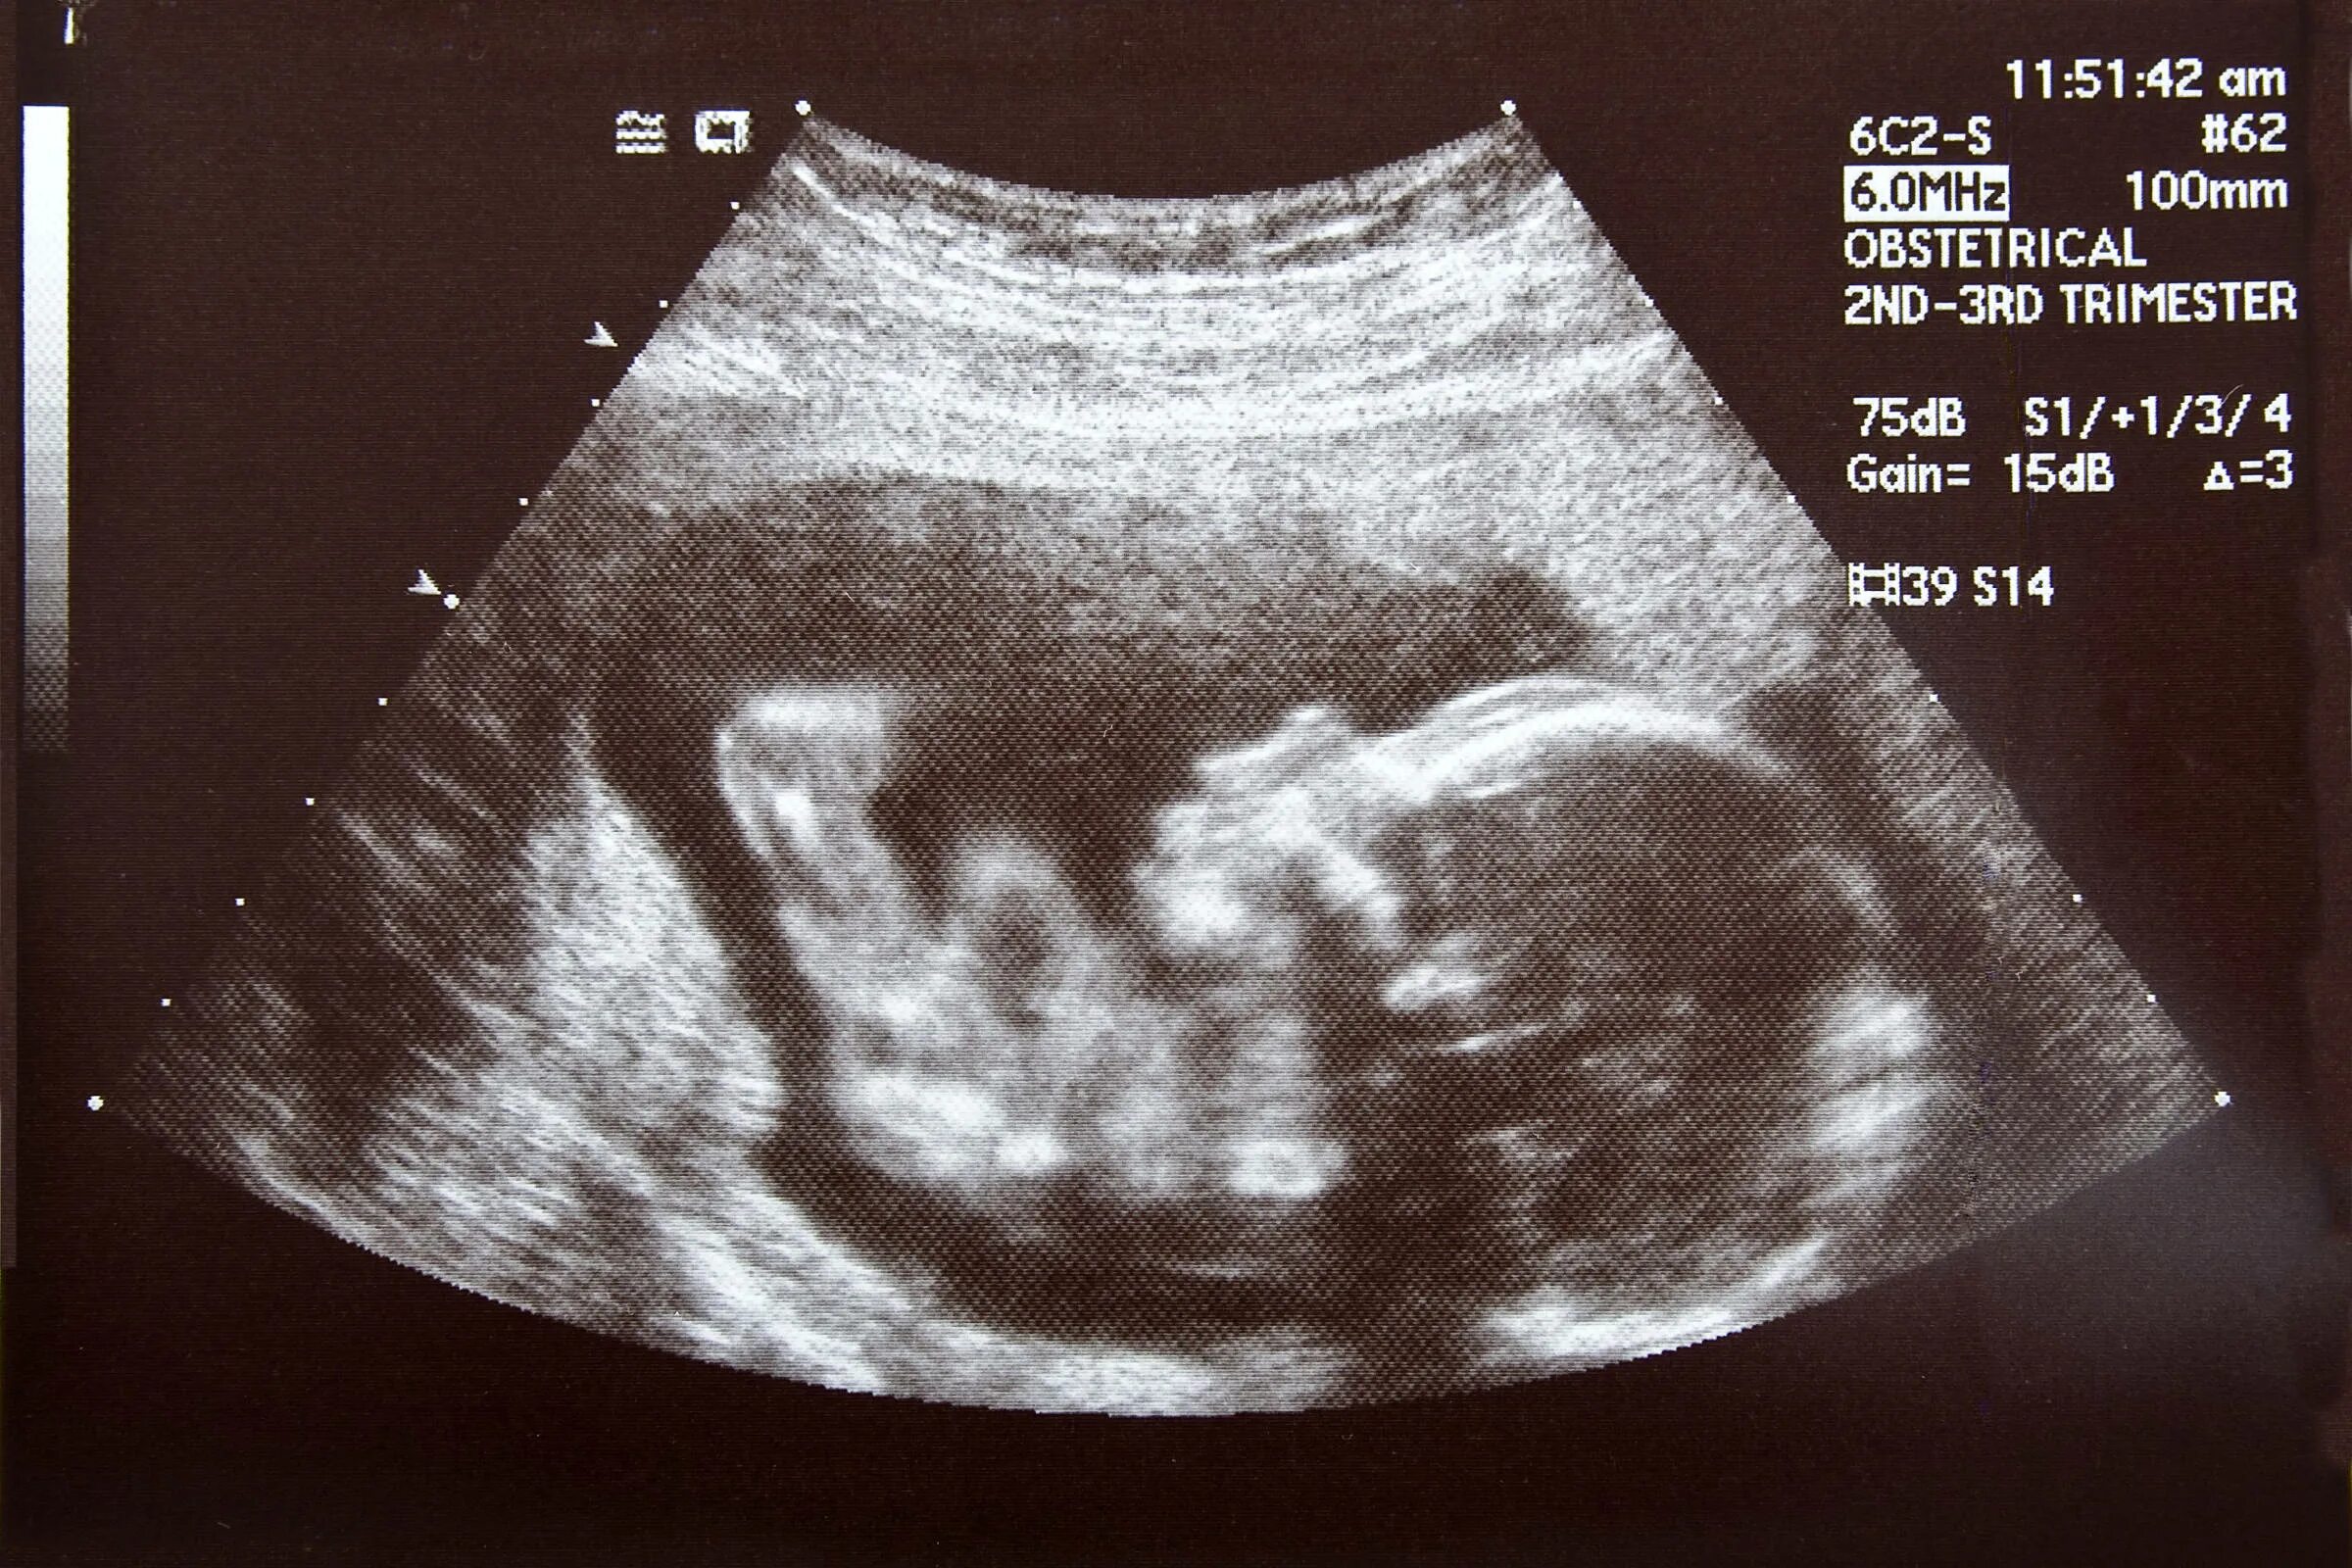

На какой неделе беременности ощущается шевеление